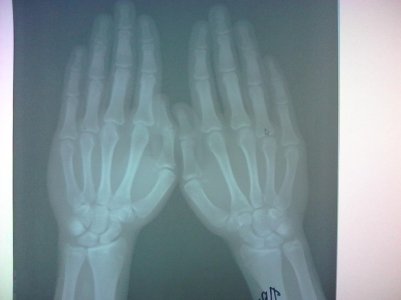

Здравствуйте. Скажите, пожалуйста, закрыты ли зоны роста на следующих снимках? Врач-эндокринолог сказала, что закрыты, но судя по прочитанным мною форумам врач может ошибаться. Врач-рентгенолог про зоны роста ничего не написала, только написала "костный возраст: 18-19 лет." Мне 18 лет, мой рост 161 см. Рост родителей: 152 см и 171 см. По направлению врача сдавал анализы на гормоны - всё в норме.